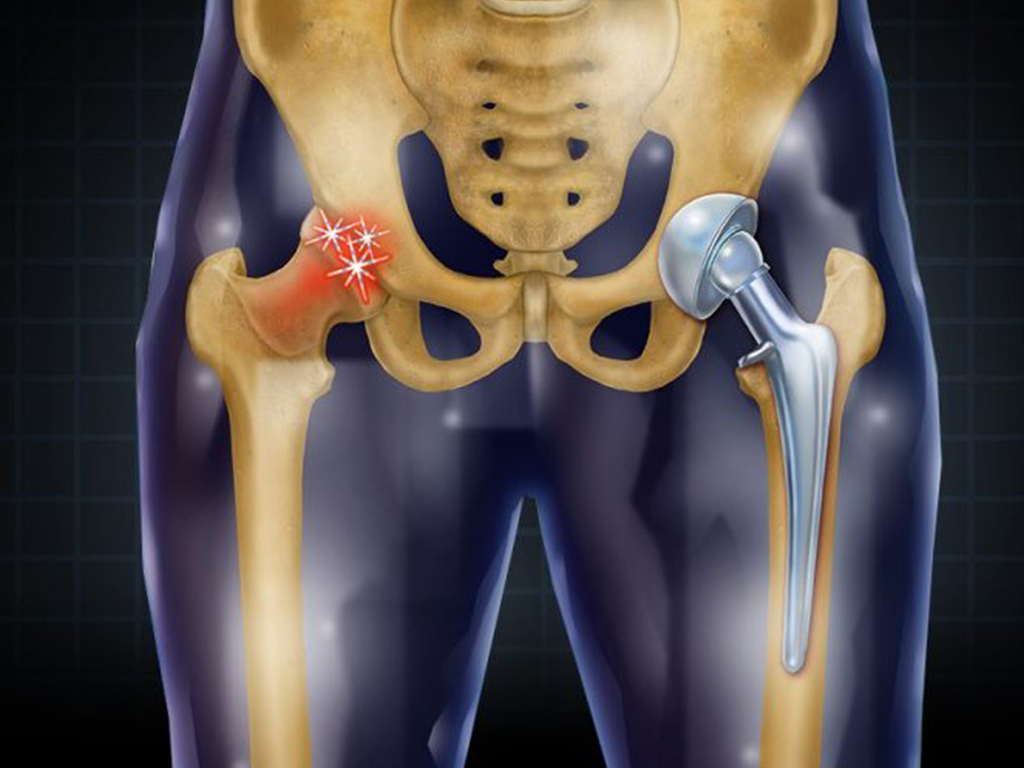

Hip replacement surgery, also known as hip arthroplasty, is a procedure where a damaged or diseased hip joint is replaced with an artificial implant. This surgery is commonly done in individuals who suffer from severe hip pain or dysfunction due to conditions like arthritis, fractures, or other joint disorders. The goal of hip replacement is to relieve pain, improve mobility, and enhance the quality of life.

- Involves removing the damaged ball (head of the femur) and socket (acetabulum) of the hip joint and replacing them with an artificial ball-and-socket joint.

- The surgeon removes the damaged femoral head (the “ball” of the hip joint) and replaces it with a metal or ceramic ball.

- The acetabulum (the “socket”) is also prepared and fitted with a new artificial cup, often made from metal, ceramic, or plastic.